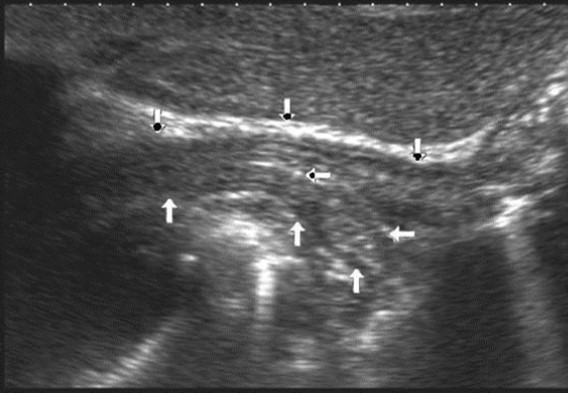

The polypoid type of gastric cancer was observed in 3 (4,9±2,8%) cases, the ulcerative type – in 18 (29,5±5,8%), the infiltrative ulcerative type – in 27 (44,3±6,4%) and the diffuse infiltrative type – in 13 (21,3%±5,2%) cases respectively (Table 2). On the echogram, the tumor was

Visualized as a polypoid formation on a wide base above the gastric mucosa of a non-uniform structure, an irregular surface (Figure 5, Figure 6, Figure 7).

Figure 5.The polypoid type of gastric carcinomas for T3 stage. On the posterior wall of the antrum, a polypoid formation with a fuzzy contour is visualized, the image of the mucous and serous membranes (arrows) is discontinuous.

Figure 6.The gastric carcinoma for T3 stage. The tumor is visualized as a polypoid formation on a wide base above the gastric mucosa of a non-uniform structure, an irregular surface (arrows).